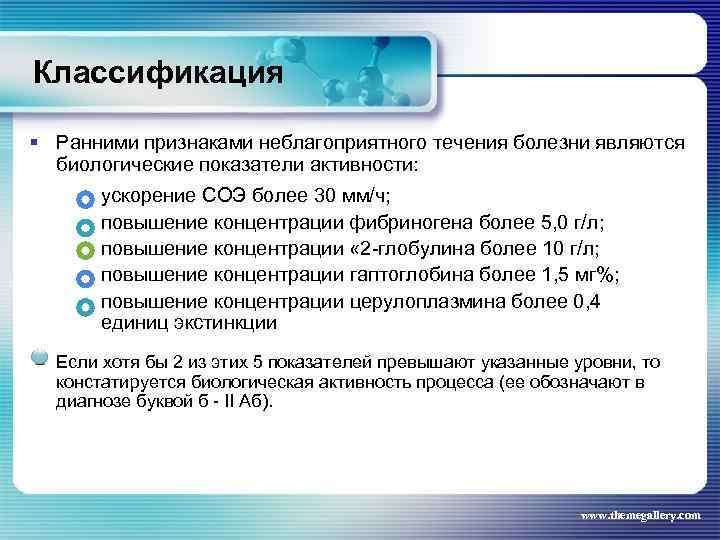

Классификация § Ранними признаками неблагоприятного течения болезни являются биологические показатели активности: ускорение СОЭ более 30 мм/ч; повышение концентрации фибриногена более 5, 0 г/л; повышение концентрации « 2 -глобулина более 10 г/л; повышение концентрации гаптоглобина более 1, 5 мг%; повышение концентрации церулоплазмина более 0, 4 единиц экстинкции Если хотя бы 2 из этих 5 показателей превышают указанные уровни, то констатируется биологическая активность процесса (ее обозначают в диагнозе буквой б - II Аб). www. themegallery. com

Классификация § Ранними признаками неблагоприятного течения болезни являются биологические показатели активности: ускорение СОЭ более 30 мм/ч; повышение концентрации фибриногена более 5, 0 г/л; повышение концентрации « 2 -глобулина более 10 г/л; повышение концентрации гаптоглобина более 1, 5 мг%; повышение концентрации церулоплазмина более 0, 4 единиц экстинкции Если хотя бы 2 из этих 5 показателей превышают указанные уровни, то констатируется биологическая активность процесса (ее обозначают в диагнозе буквой б - II Аб). www. themegallery. com